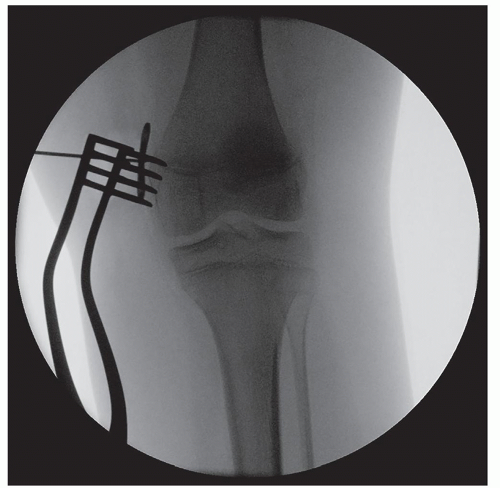

Fluoroscopy is used to identify the medial (genu valgum) or lateral (genu varum) distal femoral or proximal tibial physis (Figure 26.3)

Place central guidewire or Keith needle by free hand in center hole 8-plate (Figure 26.7), check fluoroscopic images and adjust as necessary (Figure 26.8). Also be sure to confirm visually or with freer that no soft tissue is caught under the plate

It is critical to have perfect lateral of the knee prior to assessing the sagittal placement of the plate. Do not use a “figure-4” lateral view, but instead swing the C-arm to a true lateral image

Check fluoroscopic anteroposterior (AP) (Figures 26.11 and 26.12) and then true lateral views until plate is optimally positioned (Figure 26.13)

Remove the guidewires and obtain a final fluoroscopic AP and lateral image (Figures 26.18 and 26.19). It is good to check the oblique images as well